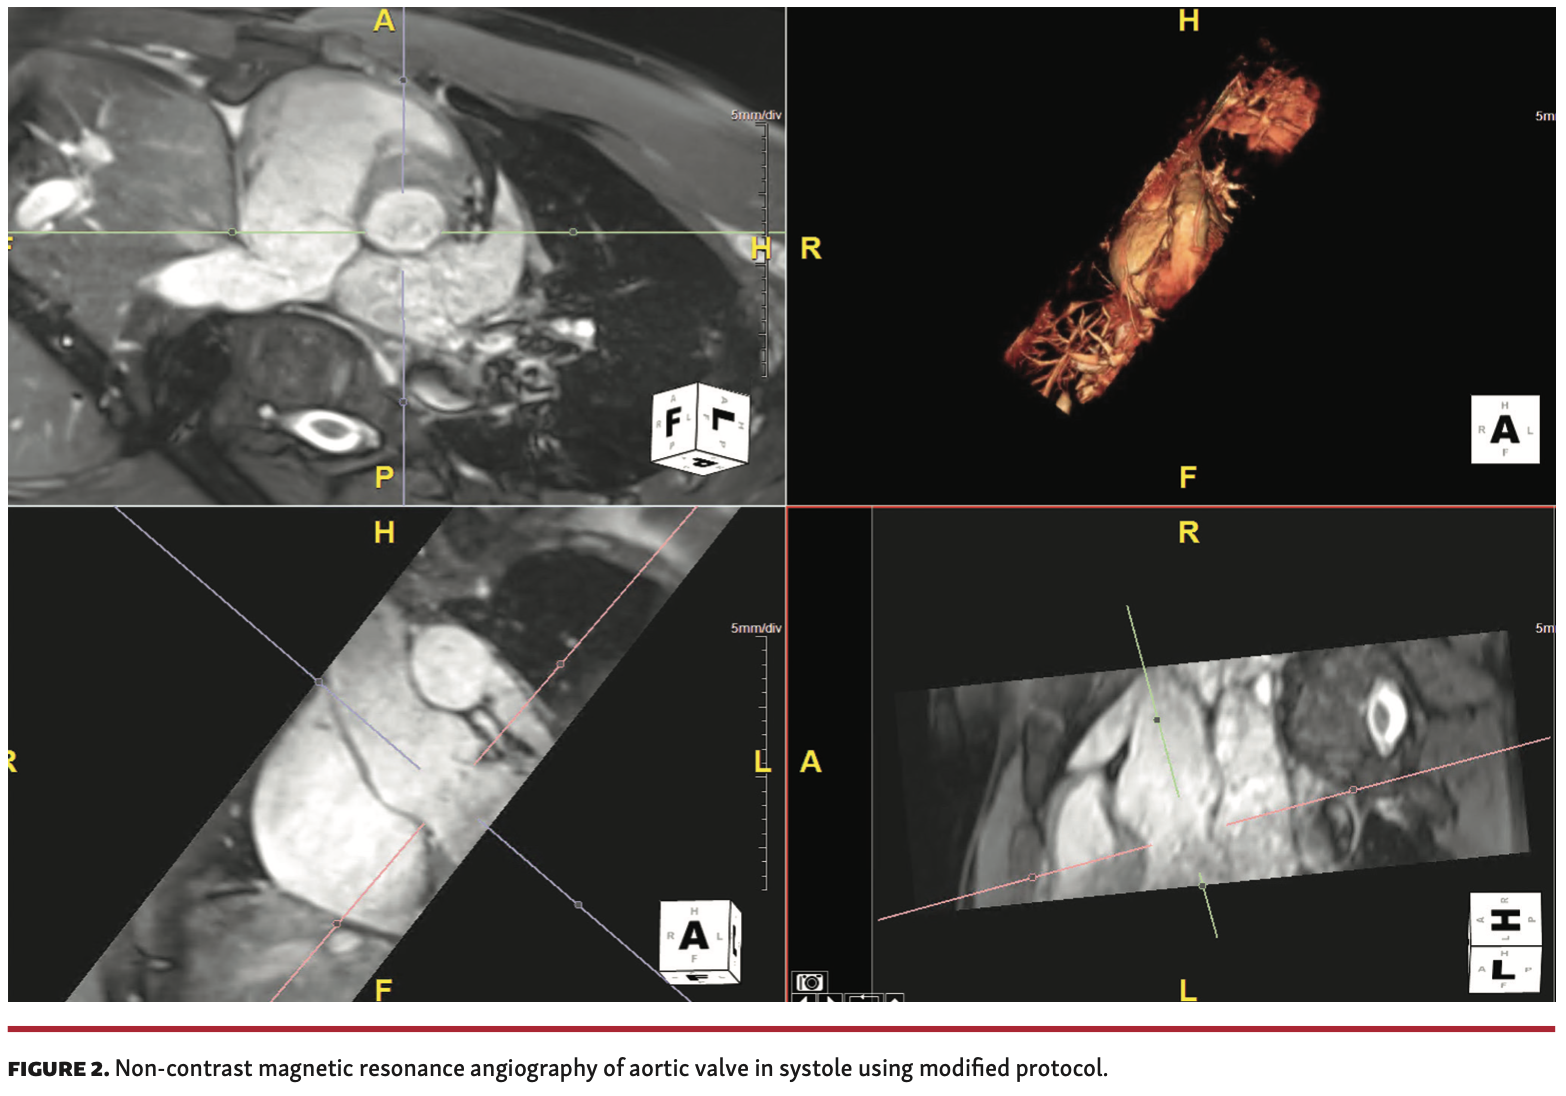

Non-contrast cardiovascular magnetic resonance (CMR) imaging. Renker et al reported the feasibility of a novel, non-contrast, free-breathing, self-navigated 3D (SN3D) MR sequence for imaging of the aortic root to the iliofemoral run-off in comparison with non-contrast 2-dimensional (2D) balanced steady-state free-precession (bSSFP) imaging.28 Non-contrast 3D-CMR may be considered as an alternative to CTA, as it has been shown to be comparable to CTA in the assessment of aortic annular sizing with adequate image quality in small patient cohorts.29 Non-contrast MRI has also proved to be a feasible and accurate method of assessing the aorto-iliac vessels when compared to CTA.30

While non-contrast CMR is a very attractive alternative to CTA, it may not be readily available at many medical institutions. Moreover, the validation studies have used 1.5 T scanners and may not be extrapolated to 3.0 T scanners. Appendix 2 summarizes the general cardiac MRI protocol used at our institution. Validation studies with a modified protocol are currently ongoing, and our results will be reported in subsequent manuscripts. An example of a non-contrast MRA of a normal aortic valve using our modified protocol is provided (Figure 2).